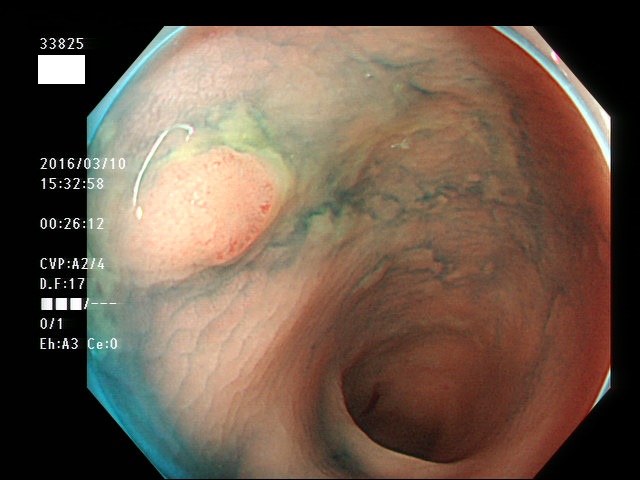

上記100名より抽出した平坦・陥凹型腺腫(=癌化の危険が高いが見落としやすい病変)の内視鏡写真